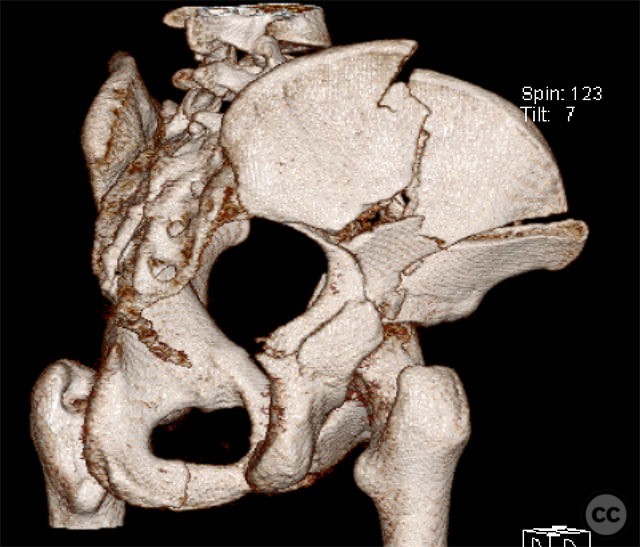

Clinical and radiological findings:  A 19-year-old female sustained a high-energy injury in a motor vehicle accident. Initial AP pelvic radiograph demonstrated a right-sided, displaced, comminuted associated both column acetabular fracture (AO/OTA 62C3), with a separate fracture fragment involving the greater sciatic notch (GSN). The right sacroiliac (SI) joint was incompletely disrupted. Surface rendered CT images confirmed the complex fracture morphology, including the separate GSN fragment and the SI-sacral injury, which rendered the typical posterior iliac fragment non-intact. Axial CT at the acetabular dome level revealed multiple displaced fragments and provided further detail regarding soft tissue involvement.